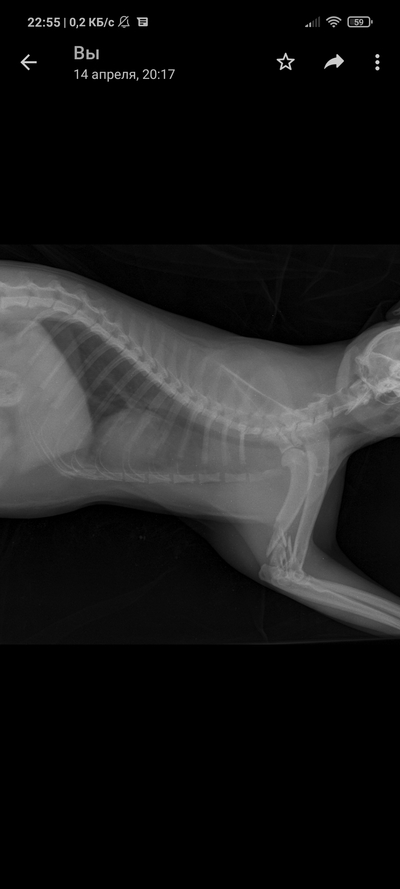

Так уж получилось что я ветеринарный врач, работаю в интенсивной терапии - принимаю и лечу самых тяжелых животных. На днях ближе к ночи прибегает женщина с котом, который шлёпнулся перед ней на улице. При осмотре выясняется что кот в шоке - лежит на боку, без давления, температуры, у него сломаны передние лапы, лицо, пневмоторакс и немного жидкости в брюшной полости (вероятно кровь). Женщина оставляет двадцатку на первые сутки и идет искать хозяина, кот помещается в стационар для стабилизации состояния. Всю ночь я ебусь с этим котом, вывожу его из шока, спускаю ему пневмоторакс, грею, обезболы льются рекой, к утру кот похож на кота, а не на покойника - начал садиться, ползать, полизал еду.

В общем, четвертый день от падения, полет нормальный, кот начал есть сам, а я иду на смену, ждите новостей, думаю скоро будет пост про то, как мы оперируем животных, в частности собираем ходули герою этой истории 😁